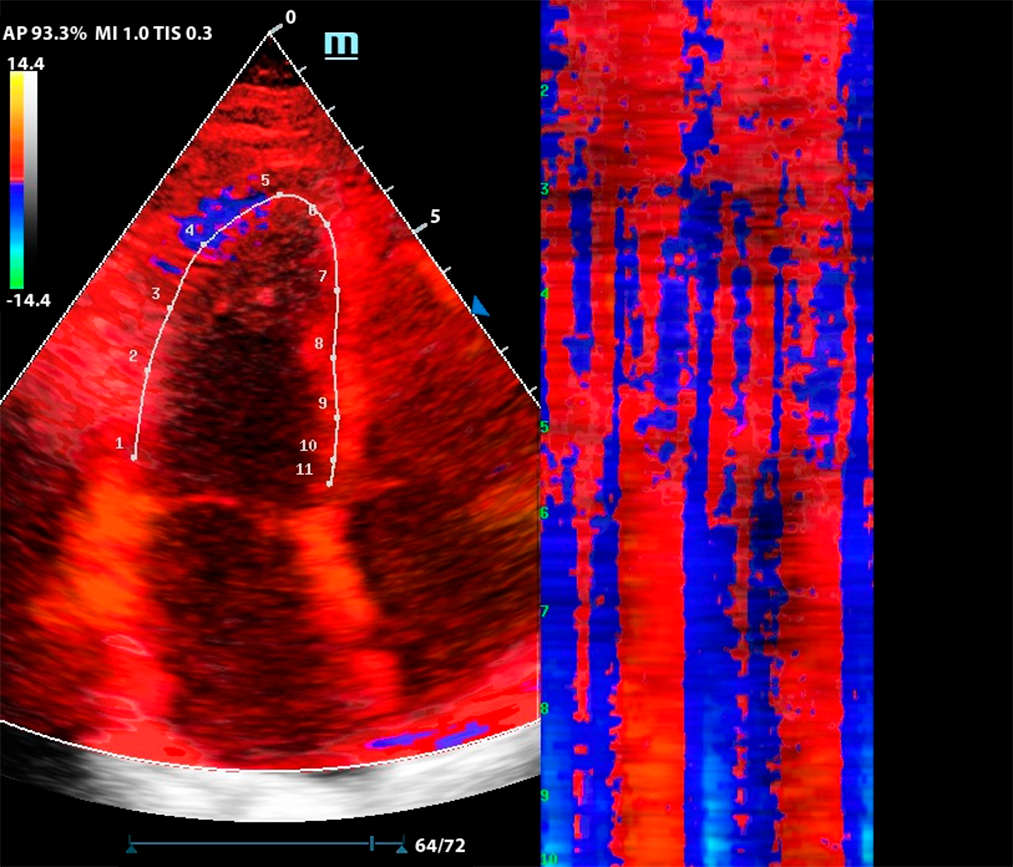

Комбинация функций TDI и Free Xros CM

М-режим — один из наиболее старых методов сканирования. Более современная версия — это свободный М-режим, который также называют Free Xros M. Однако, технология не остановилась на этом и на современных УЗ аппаратах доступен изогнутый М-режим - Free Xros CM.

Функция изогнутого М-режима особенно интересна в комбинации с тканевым допплером (TDI). Оконтуривание миокарда в цветовой карте TDI позволяет оценить кинетику левого желудочка посегментно, в виде цветовой карты на графике Free Xros CM.

Метод разворачивает левый желудочек в плоскую палитру движений за счет окраски тканевого допплера, это позволяет сравнить кинетику в каждом моменте цикла сокращения и расслабления.